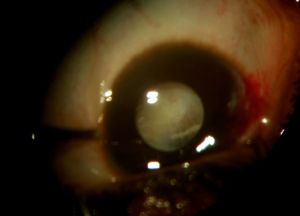

In the eye, larvae of Pentastomidae reside with a decreasing frequency in the anterior chamber, ocular adnexa, or the posterior chamber.[1] A recent case report also suggests an intracapsular location. [21] Depending on their location, they can manifest in different ways and/or induce:

- Cyclitic membrane [1]

Intraocular pentastoma nymphs can induce dramatic intraocular inflammation and mechanical damage resulting in corneal decompensation, lens melting or retinal detachment. These can ultimately lead to blindness.

The prognosis of ocular pentastomiasis depends on the time needed to make the diagnosis, on the evolutionary stadium of the larvae and on its location in the eye with a permanent decrease of visual acuity in 69% and a total visual loss in 31% of reported cases. [1]